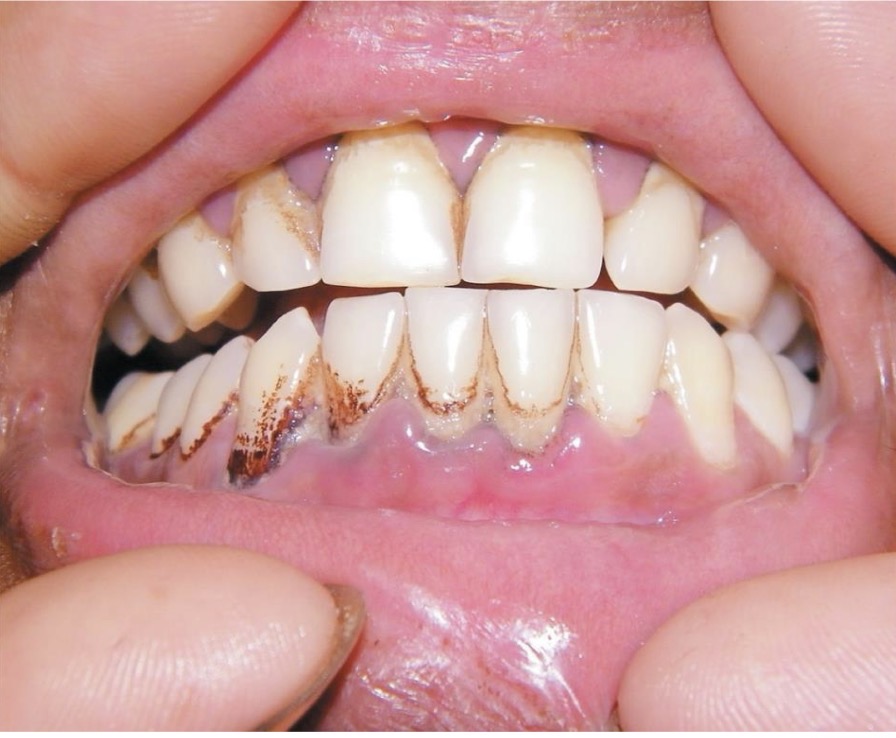

BN NAM

HÚT THUỐC LÁ LÂU NĂM

CHẨN ĐOÁN?

VIÊM MIỆNG DO HÚT THUỐC LÁ

BN NAM, HÚT THUỐC LÂU NĂM

NỔI CÁC NỐT ĐỎ Ở VÒM MIỆNG

CHẨN ĐOÁN ?